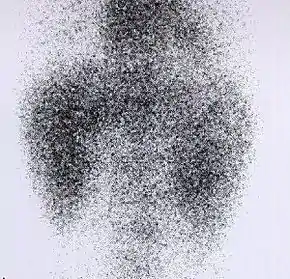

DMSA scan

Decreased Tc99m-DMSA uptake in both kidneys, suggestive of renal failure.

A DMSA scan is a radionuclide scan that uses dimercaptosuccinic acid (DMSA) in assessing renal morphology, structure and function. Radioactive technetium-99m is combined with DMSA and injected into a patient, followed by imaging with a gamma camera after 2-3 hours.[1] A DMSA scan is usually static imaging, while other radiotracers like DTPA and MAG3 are usually used for dynamic imaging to assess renal excretion.[2]